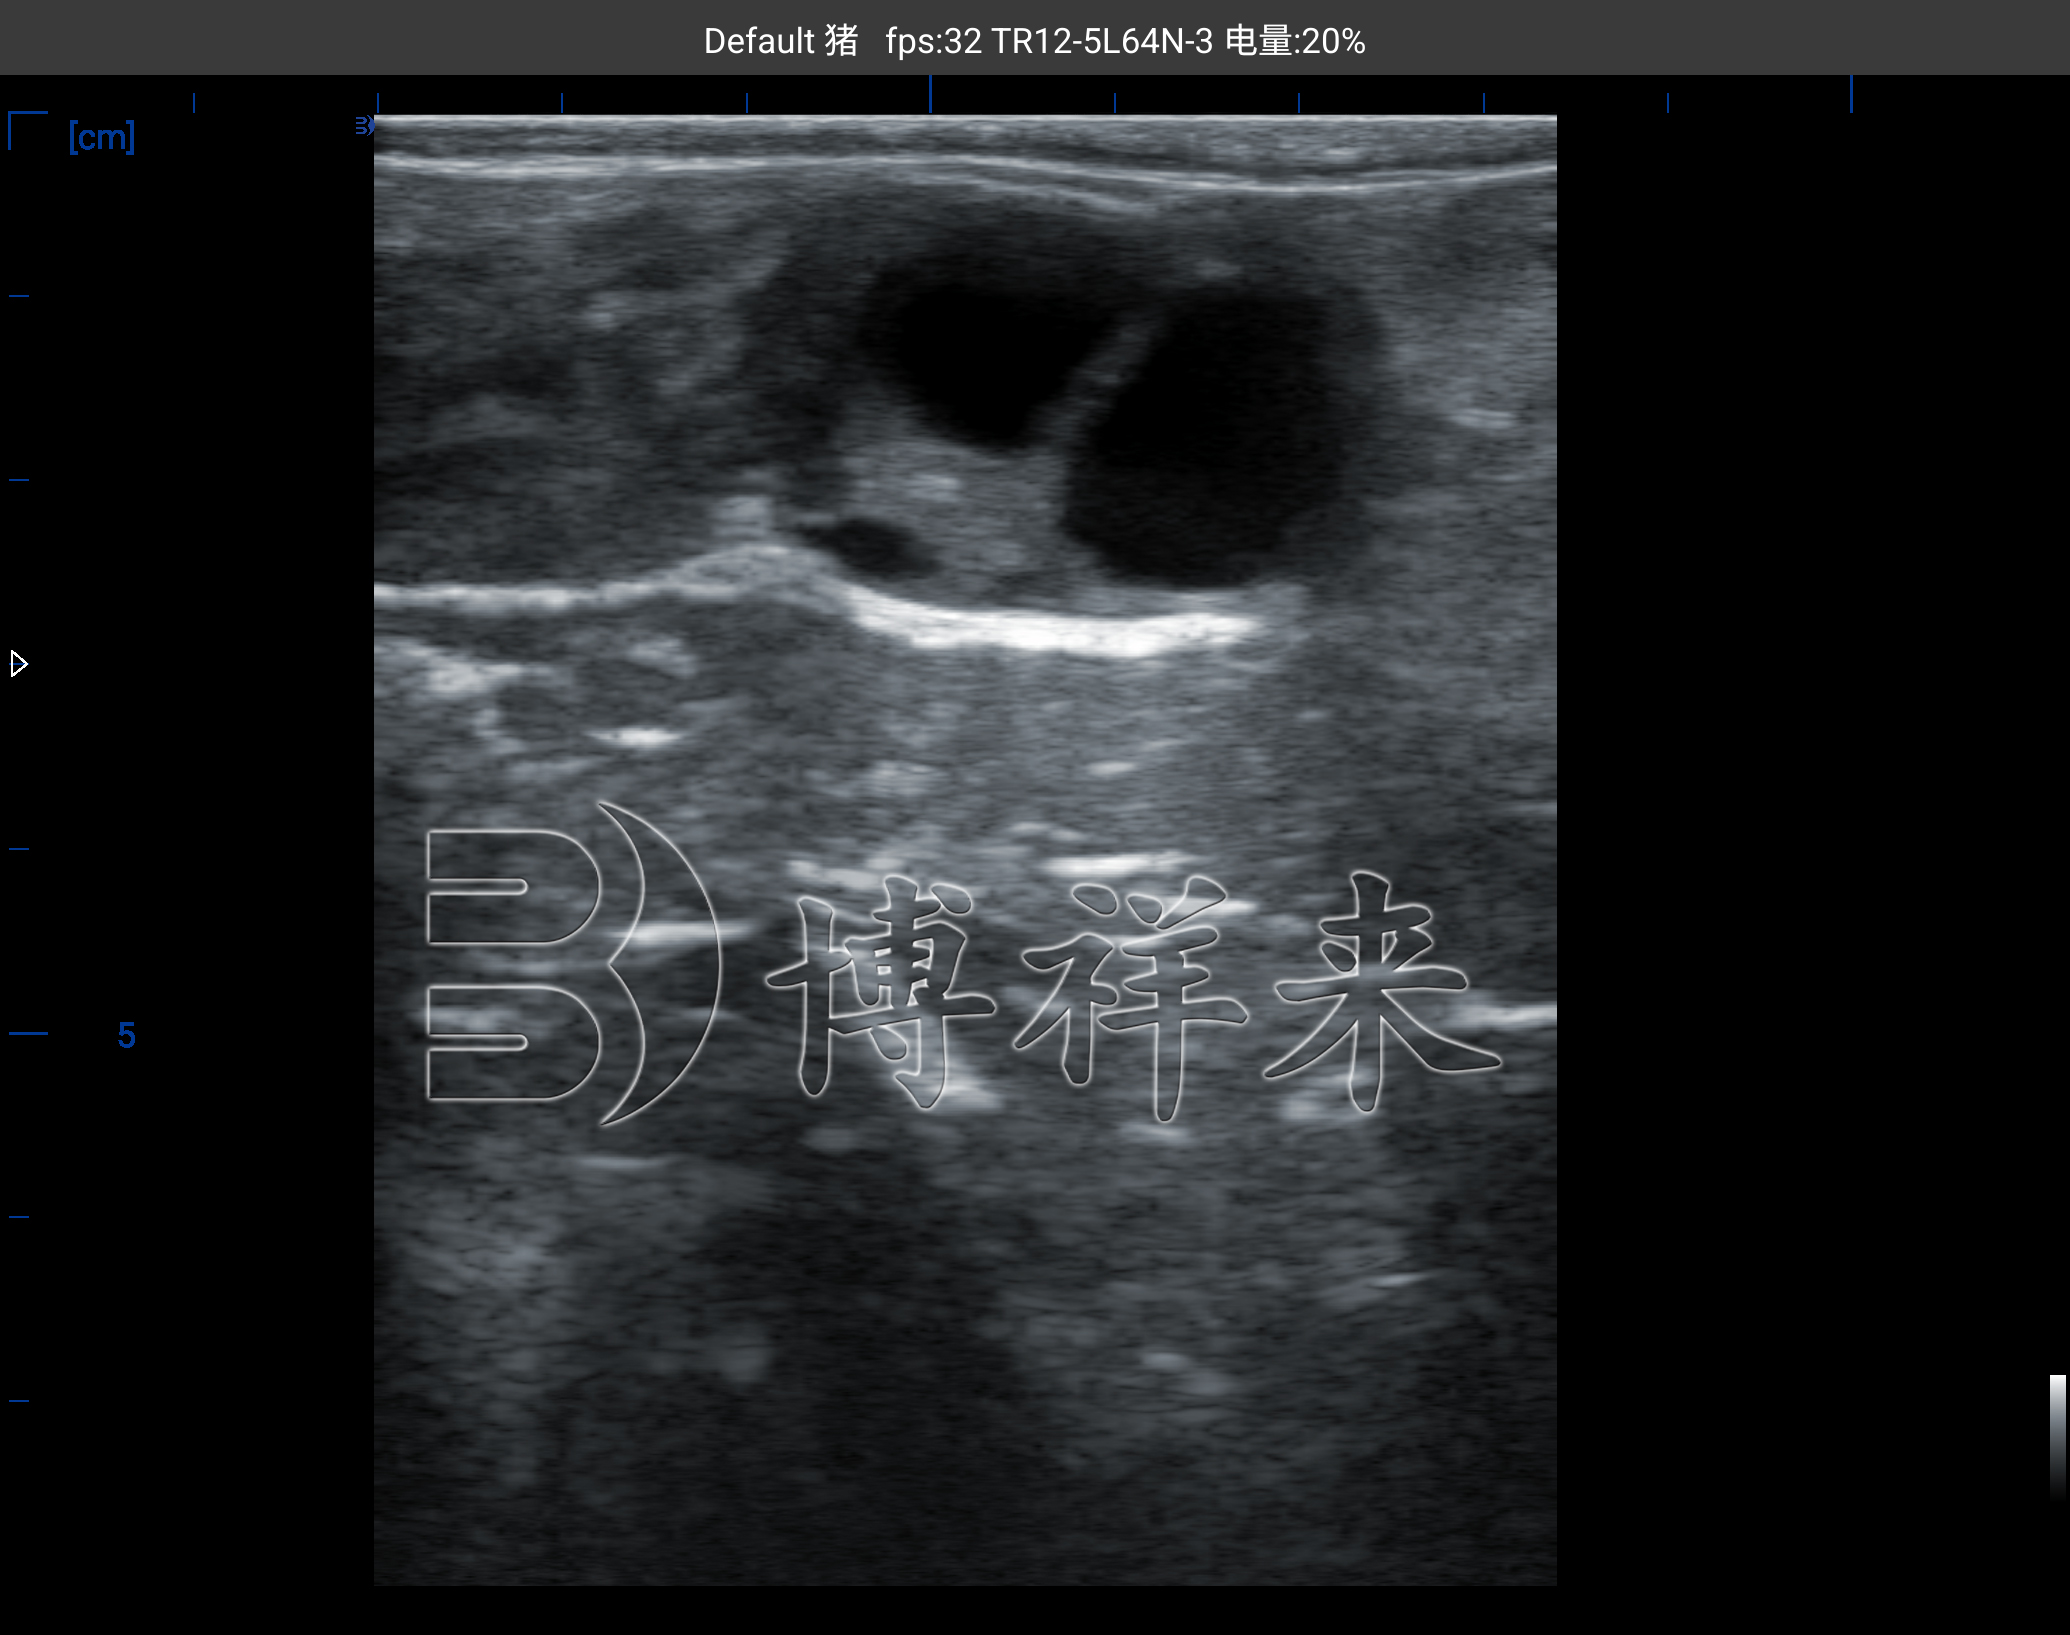

优势卵泡(直径>10 mm):边界光滑清晰,液腔直径较大,是即将排卵的重要信号。

当优势卵泡逐渐发育并接近排卵时,B超能直观显示其形态。结合黄体检测和行为学观察,可以更准确地把握授精时机,提高受孕率。

在一些母牛中,可能出现卵泡囊肿或黄体持续不退的情况。B超能够帮助区分卵泡与囊肿,避免错误的繁殖管理决策。